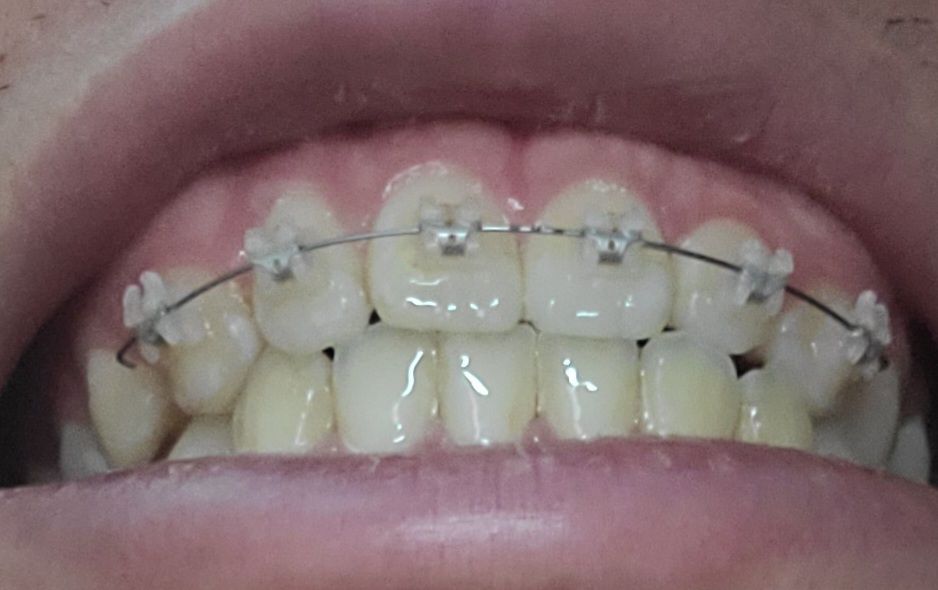

이를 앙 다물고 찍은 사진입니다

절단 교합은 상 하악 앞니가 정확히 일직선으로 맞물려야 합니다. 따라서 지금 정도로 절단교합이라고 하지 않습니다. 또한 음식 섭취 시 앞니는 음식을 간단히 끊는 용도이지 실제로는 어금니가 모든 역할을 합니다. 따라서 해당 치아가 현재로 맞물린다고 해서 마모되지 않습니다. 지금 정도는 교정 중이기 때문에 잘못되었다고 볼수도 없고 절단교합 및 이상이라고 하지 않습니다. 치료를 충실히 받으시길 바랍니다.

절단교합은 위아래 치아의 끝부분끼리 정확하게 맞닿는 상태를 의미합니다.

사진으로는 오른쪽은 절단교합이 아닌 정상교합이며, 왼쪽은 측절치가 애매하게 보이긴 합니다.

말그대로 절단교합은 앞니 끝과 아래니의 끝이 교합이 되는 상태를 말합니다. 사진상으로 보면 절단교합은 아니신거 같아요.